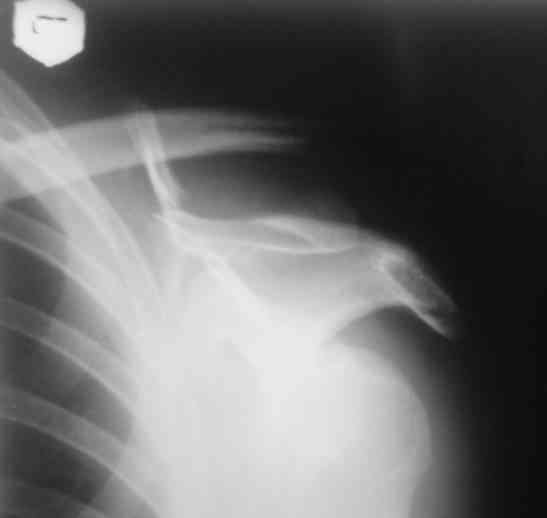

Планирую через четыре недели сделать рентген-контроль с решением вопроса об удалении АВФ. Аппарат смонтирован из деталей аппарата Илизарова. Картинки в приложении.

К сожалению оригинального аппарата Сушко нет в наличии (даже в глаза не видел), но использовался сам принцип метода по Сушко-Илизарову. Цитирую из "Основ по чрезкостному остеосинтезу аппаратом Г.И. Илизарова" (Л.Н.Соломин, 2005): 1. В каждый костный фрагмент должно быть введено не менее двух 2-мм консольных спиц, расположенных под углом к друг другу. 2. Места введения спиц должны располагаться вблизи суставных концов ключицы.

3. Точки введения спиц должны находиться на верхней поверхности ключицы.

4. Плоскость расположения спиц должна совпадать с продольной осью костных фрагментов.

5. При диафизарных переломах спицы проводят через оба кортикальных слоя.

6. При переломо-вывихах акромиального конца ключицы консольные спицы в акромиальный конец ключицы вводят только до упора в противолежащий

кортикальный слой; в акромиальный отросток лопатки консольные спицы не вводят, а используют спицу Киршнера "acr.,6-12", концы которой П-образно загибают навстречу друг другу.

7. Расстояние между поверхностью кожи и внешними опорами должно быть минимальным - в пределах 1,5-2 см.

лопатки купировались через 24 часа после операции. Не смотря на громоздкость конструкции аппара т переносится самим больным легко. Под спортивной курткой не так и заметно. Разрешил мытье под душем с последующей заменой прижимных спиртовых шариков, обработкой АВФ и спиц спиртом 1 раз в неделю. Больной пробыл в отделении 3 койко-дня с дальнейшим долечиванием амбулаторно.